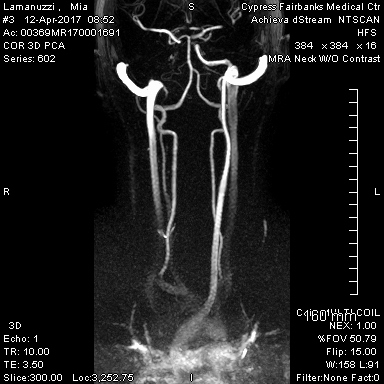

Wednesday 4/12

Wednesday morning, we finally

got to meet with the vascular surgeon, who recommended that I be transferred to

another hospital for an angiogram. He

was the first person to mention the possibility of FMD being involved. I got another MRI – this time it was an MRA of my neck. After lunch I finally took a shower, which

![]() |

| Can you spy what's missing on this MRA? Hint: my right side is shown on the left of the image. |